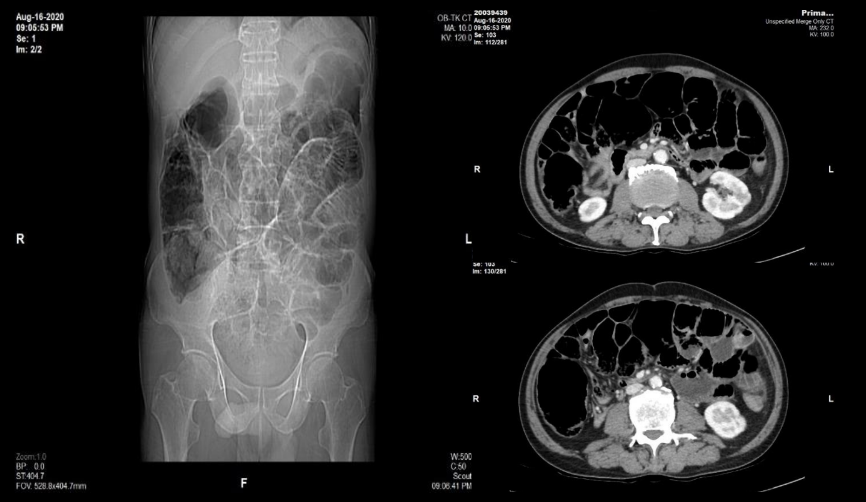

- BN nam 71T vào Vinmec cấp cứu lúc 23h30 (8/2020) vì đau bụng quanh rốn từng cơn, bụng chướng kèm bí trung đại tiện, nôn. BN đã vào BV huyện địa phương, chụp XQ bụng đứng có hình ảnh các quai ruột giãn + mức hơi-dịch. CT Scan bụng không thuốc (15h30 cùng ngày) nhiều quai ruột giãn chủ yếu 1/2 bụng phải.

- Xét nghiệm: Ure 9.1 Crea 105, GOT/GPT 21.0/24.9, D-Dimer 1007, WBC 18.600 (N90.5%), K+ 4.3, Na+ 139, Cl- 94.9 CT bụng (Vinmec):- Hình ảnh một số quai hỗng tràng và hồi tràng giãn, vài quai trong lòng chứa phân (dấu hiệu Feces sign), hình mức nước hơi không điển hình, không thấy rõ quai ruột giãn cạnh quai ruột xẹp, không thấy dấu hiệu xoáy nước. Đề nghị phối hợp thêm lâm sàng.

- Manh tràng và đại tràng ngang giãn trong lòng chứa nhiều khí và bã thức ăn (Manh tràng dãn 6cm, dãn các quai ruột non #3.5cm)

- Hiện không thấy hẹp tắc các ĐM, TM mạc treo tại thời điểm khảo sát.